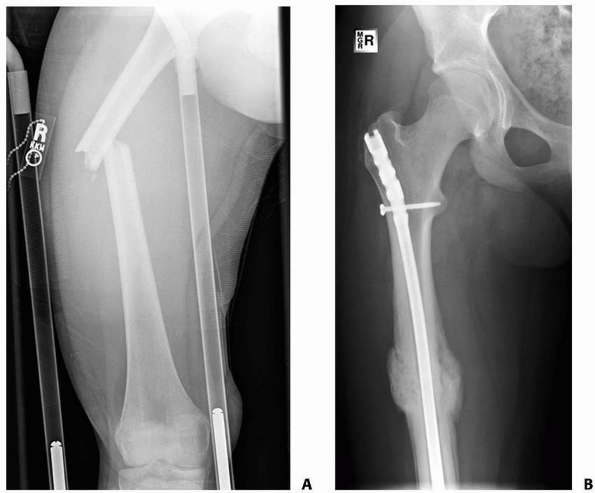

![]() |

FIGURE 22-21 A.

This proximal spiral femur fracture was deemed length-unstable and a poor candidate for titanium elastic nails. The surgeon chose an external fixator, rather than a plate. B. Eight weeks after injury, the fracture is healing in excellent alignment and there is good early callus. Fixator removal is easier than plate removal. |